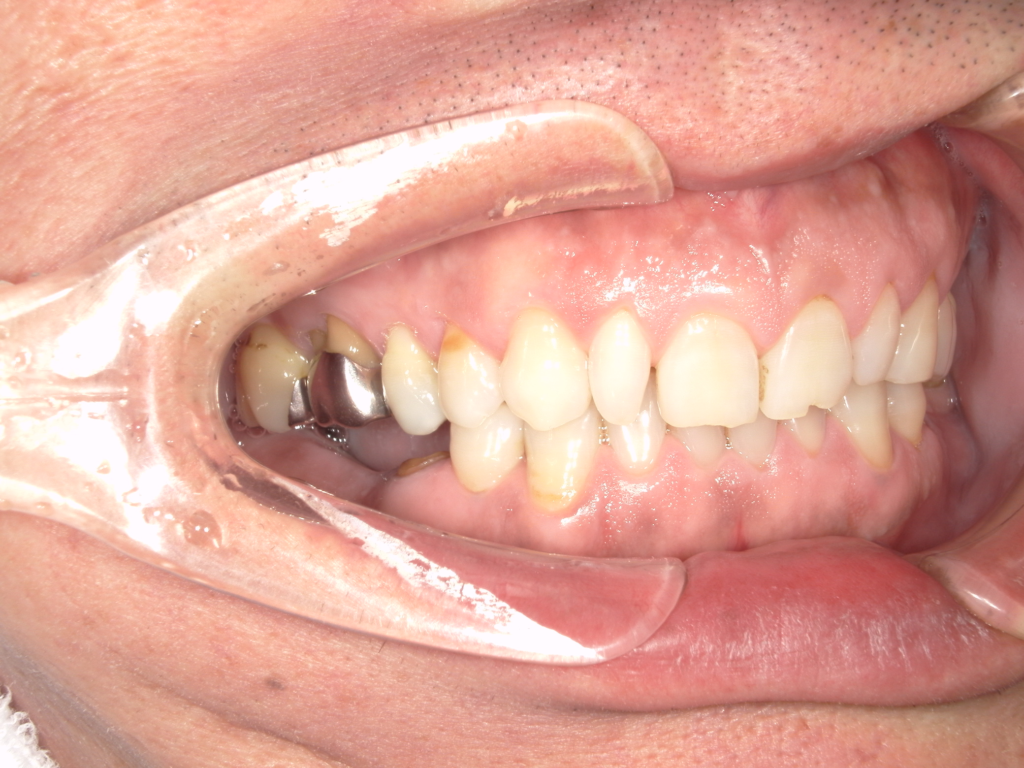

Y様インプラント実例 #44

左の上下の奥歯をインプラントで治療しています。

左下の奥歯は歯を抜くのと同時にインプラントの埋め込みを行っています。

被せものは上下、セラミックスで作っています。

治療前

治療後